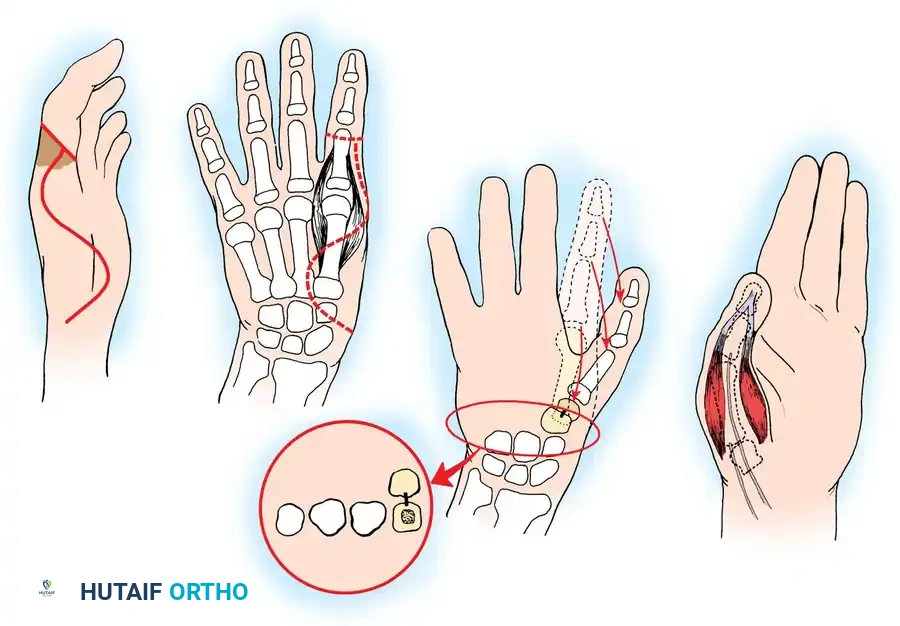

The Moberg Advancement Flap

Amputation stumps that are painful due to thin skin coverage at the pulp and nail junction can be significantly improved by utilizing a limited volar advancement flap, classically described by Moberg.

Surgical Principles of the Moberg Flap:

* Design: The flap is outlined over the volar aspect of the digit, incorporating both neurovascular bundles to ensure robust perfusion and preserved sensibility.

* Elevation: The flap is raised deep to the neurovascular bundles, separating them from the flexor tendon sheath.

* Advancement: The flap is advanced distally (typically up to 1.5 cm) to cover the terminal defect.

* Limitations: In the fingers (unlike the thumb), proximal dissection to develop these flaps should not extend proximal to the proximal interphalangeal (PIP) joint. Extending beyond this point risks devascularization and severe flexion contractures.

🔪 Surgical Technique: Metacarpal Lengthening and Local Flap (Gillies-Millard "Cocked Hat" Procedure)

When amputation occurs at the metacarpophalangeal joint or within the condylar area of the first metacarpal, the intrinsic thenar musculature is preserved. The Gillies-Millard technique lengthens the skeletal ray using a bone graft while advancing local sensate skin to cover the new tip.

- Incision: Make a curved, horseshoe-shaped incision around the dorsal, radial, and volar aspects of the base of the thumb.

- Flap Elevation: Undermine the skin distally, staying strictly superficial to the main venous drainage network to prevent venous congestion and subsequent flap necrosis. Continue undermining until a hollow, thimble-like flap has been elevated and slipped off the end of the bony stump. The blood supply to this flap is maintained via the arborization of vessels around the base of the index finger in the thumb web.